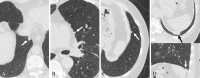

Background Pulmonary noncalcified nodules (NCNs) attached to the fissural or costal pleura with smooth margins and triangular or lentiform, oval, or semicircular (LOS) shapes at low-dose CT are recommended for annual follow-up instead of immediate workup. Purpose To determine whether management of mediastinal or diaphragmatic pleura-attached NCNs (M/DP-NCNs) with the same features as fissural or costal pleura-attached NCNs at low-dose CT can follow the same recommendations. Materials and Methods This retrospective study reviewed chest CT examinations in participants from two databases. Group A included 1451 participants who had lung cancer that was first present as a solid nodule with an average diameter of 3.0-30.0 mm. Group B included 345 consecutive participants from a lung cancer screening program who had at least one solid nodule with a diameter of 3.0-30.0 mm at baseline CT and underwent at least three follow-up CT examinations. Radiologists reviewed CT images to identify solid M/DP-NCNs, defined as nodules 0 mm in distance from the mediastinal or diaphragmatic pleura, and recorded average diameter, margin, and shape. General descriptive statistics were used. Results Among the 1451 participants with lung cancer in group A, 163 participants (median age, 68 years [IQR, 61.5-75.0 years]; 92 male participants) had 164 malignant M/DP-NCNs 3.0-30.0 mm in average diameter. None of the 164 malignant M/DP-NCNs had smooth margins and triangular or LOS shapes (upper limit of 95% CI of proportion, 0.02). Among the 345 consecutive screening participants in group B, 146 participants (median age, 65 years [IQR, 59-71 years]; 81 female participants) had 240 M/DP-NCNs with average diameter 3.0-30.0 mm. None of the M/DP-NCNs with smooth margins and triangular or LOS shapes were malignant after a median follow-up of 57.8 months (IQR, 46.3-68.1 months). Conclusion For solid M/DP-NCNs with smooth margins and triangular or LOS shapes at low-dose CT, the risk of lung cancer is extremely low, which supports the recommendation of Lung Imaging Reporting and Data System version 2022 for annual follow-up instead of immediate workup. © RSNA, 2024 See also the editorial by Goodman and Baruah in this issue.